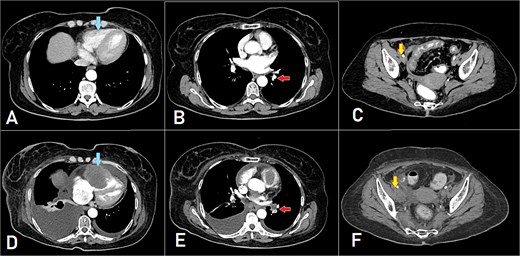

After 8 months of CapeOX-bevacizumab treatment, she was switched to DeGramont-bevacizumab due to neuropathy, receiving seven cycles. The patient later elected to discontinue treatment and was lost to follow-up. Seven months later, she presented with dyspnea on minimal exertion. Laboratory tests were within normal limits; however, a CT scan disclosed a new soft tissue density in the right ventricle, measuring up to 6 cm, suggestive of intracardiac involvement. Imaging findings were consistent with a differential of thrombus versus metastatic lesion. Additionally, filling defects of contrast opacification were observed in the right upper and left lower segmental and subsegmental pulmonary artery branches, indicative of concurrent pulmonary embolisms. A new right external iliac lymph node enlargement was also identified. The overall clinical and radiological assessment was consistent with disease progression (Fig. 3).

A, B, and C displaying the baseline images. (D) A mass lesion originating from the right ventricle (arrow). (E) Filling defect in the segmental branches of the pulmonary artery representing pulmonary embolism (arrow). (F) A newly seen right para-iliac lymph node (arrow).